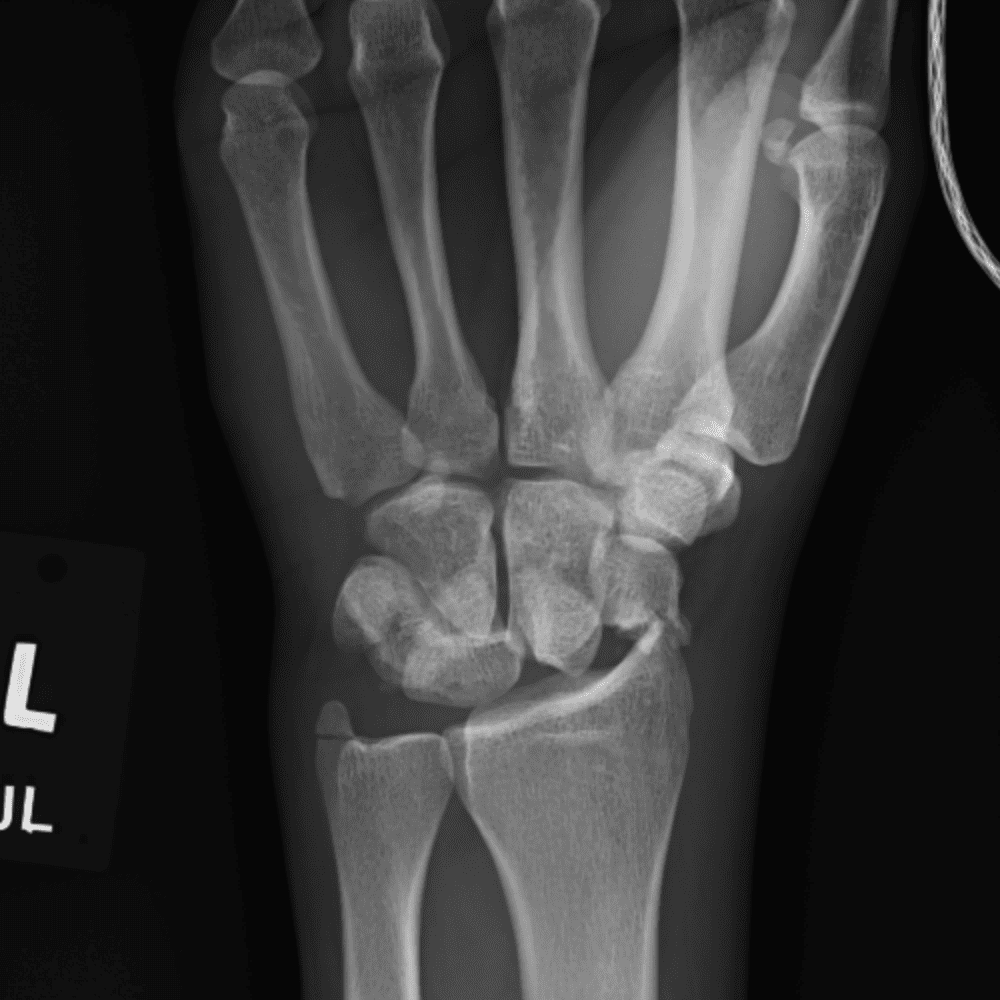

Simuliert den Dienst durch subtile oder schwierige Fälle und einige Normalbefunde.

30 Fälle